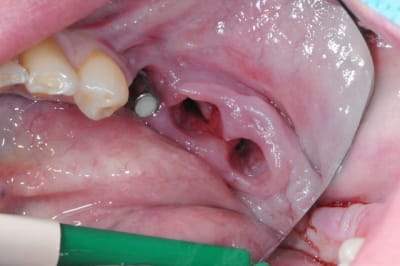

1-2-3 dépose du bridge

facile :) ça vient tout seul.

4 après un long moment de nettoyage, de curetage, de surfaçage implantaire, d'aeropolissage de l'implant, etc...

on fini enfin par arriver à ça.

ah oui, j'ai passé 2 fois un bon gros quart d'heure à gérer deux petites artères intra-osseuses de me..e qui m'ont vraiment pourri ma zénitude per-op.

de vraies petits geysers! ça doit faire dix ans que j'en avais pas eu des comme ça.